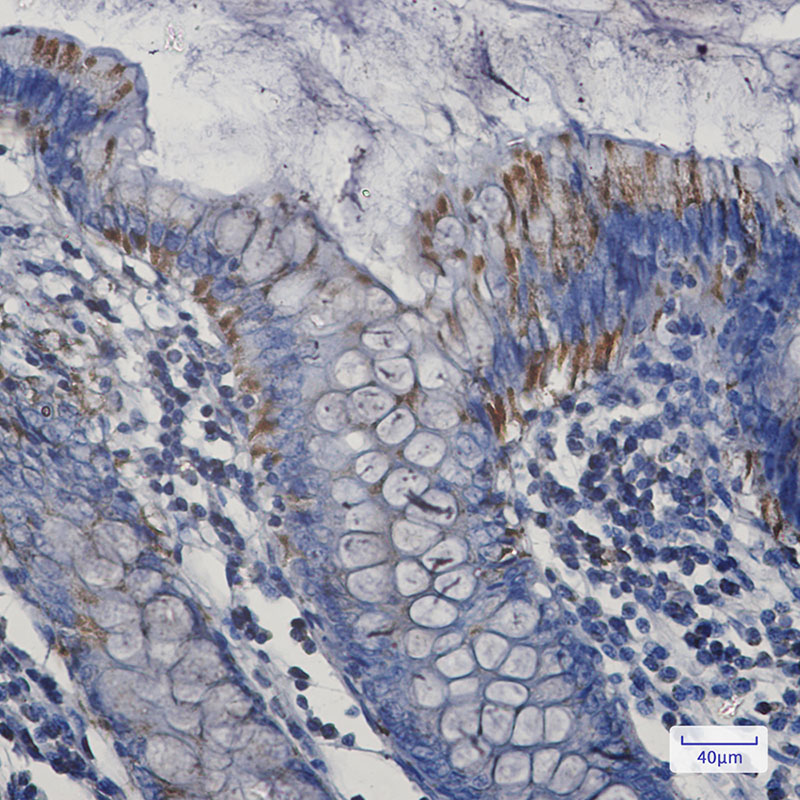

IHC 1/50-1/100 Human,Mouse,Rat